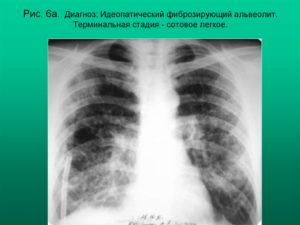

Что такое «сотовое легкое»?

Одним из самых серьезных исходов-осложнений саркоидоза является так называемое «сотовое легкое». Этот термин развился задолго до введения в повседневный обиход таких гаджетов, как сотовые телефоны и смартфоны.

«Сотовое легкое» — это патоморфологический синдром, для которого характерно образование в легочной ткани «сотов», или маленьких полостей, воздушных кист, у которых толстые стенки, из фиброзной соединительной ткани. Толщина этих стенок может достигать 3 мм.

Иными словами, эти полости – следы «отбушевавшего» аутоиммунного воспаления. В норме легочная ткань представляет собой «дышащую альвеолярную пену», а «соты» — не что иное, как головешки и угли погасшего костра. Этот феномен диагностируют рентгенологически, и его появление – неблагоприятный сигнал.

Это значит, что у пациента может скоро наступить выраженная легочная недостаточность: сильная одышка при малейшей нагрузке, такой больной будет нуждаться в частой подаче кислорода для облегчения дыхания. Понятно, что при своевременном и правильном лечении можно не доводить дело до подобных крайностей.